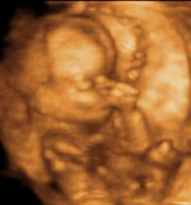

Vika 19

Nú taka tennur að myndast. Fyrst verða til vísar að fullorðinstönnum sem eru ofar en barnatennur. Framar fullorðinstönnum eru barnatennur sem myndast á næstu dögum. Barnið verður á þessum tíma mjög mikið á hreyfingu, spyrnir fótum, hristir sig, og reynir á þol kviðarins með bæði höndum og fótum. Barnið sefur einnig mikið eða um 20 klst á dag en á það til að vakna einmitt þegar móðirin ætlar að hvíla sig. Barnið er nú orðið um 21 cm á lengd og um 270 grömm.